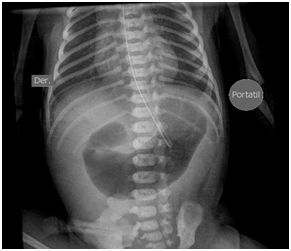

However, on day … episodes of desaturation appeared with an increase in FiO2 and ON up to 40ppm, and the patient remained under sedation. On the sixth day, milrinone was added to improve perfusion at the pulmonary level and norepinephrine was reinitiated to increase systemic blood pressure. In addition, a dose of surfactant was administered, chest radiography showed bilateral parahiliar interstitial infiltrate, peripheral pulmonary vasculature increased, and decrease in left cavities (Figure 3). Nevertheless, within a few hours she had bradycardia and hypotension, and a new echocardiogram was performed, evidencing right chambers failure and an advanced resuscitation was initiated with drug administration and cardiac massage without obtaining a response, causing patient´s death. The transfontanelar scan was normal. A karyotype was done with a normal report (46,XX).

Figure 3 Chest x-ray with pulmonary changes by HTPP.